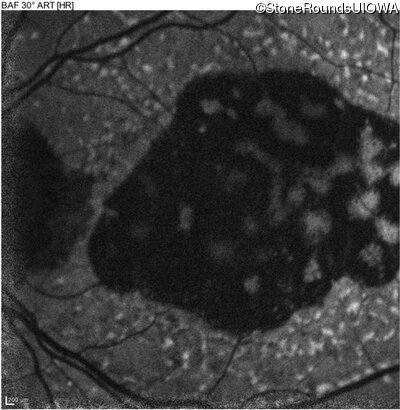

AR Stargardt Disease (IIA)

Age at visit: 59 years

This 59 year old man has noticed some blank spots near the center of his vision over the last 2 years.

AR Stargardt Disease ABCA4 Leu2027Phe CTC>TTC IVS30+1321 A>G AR